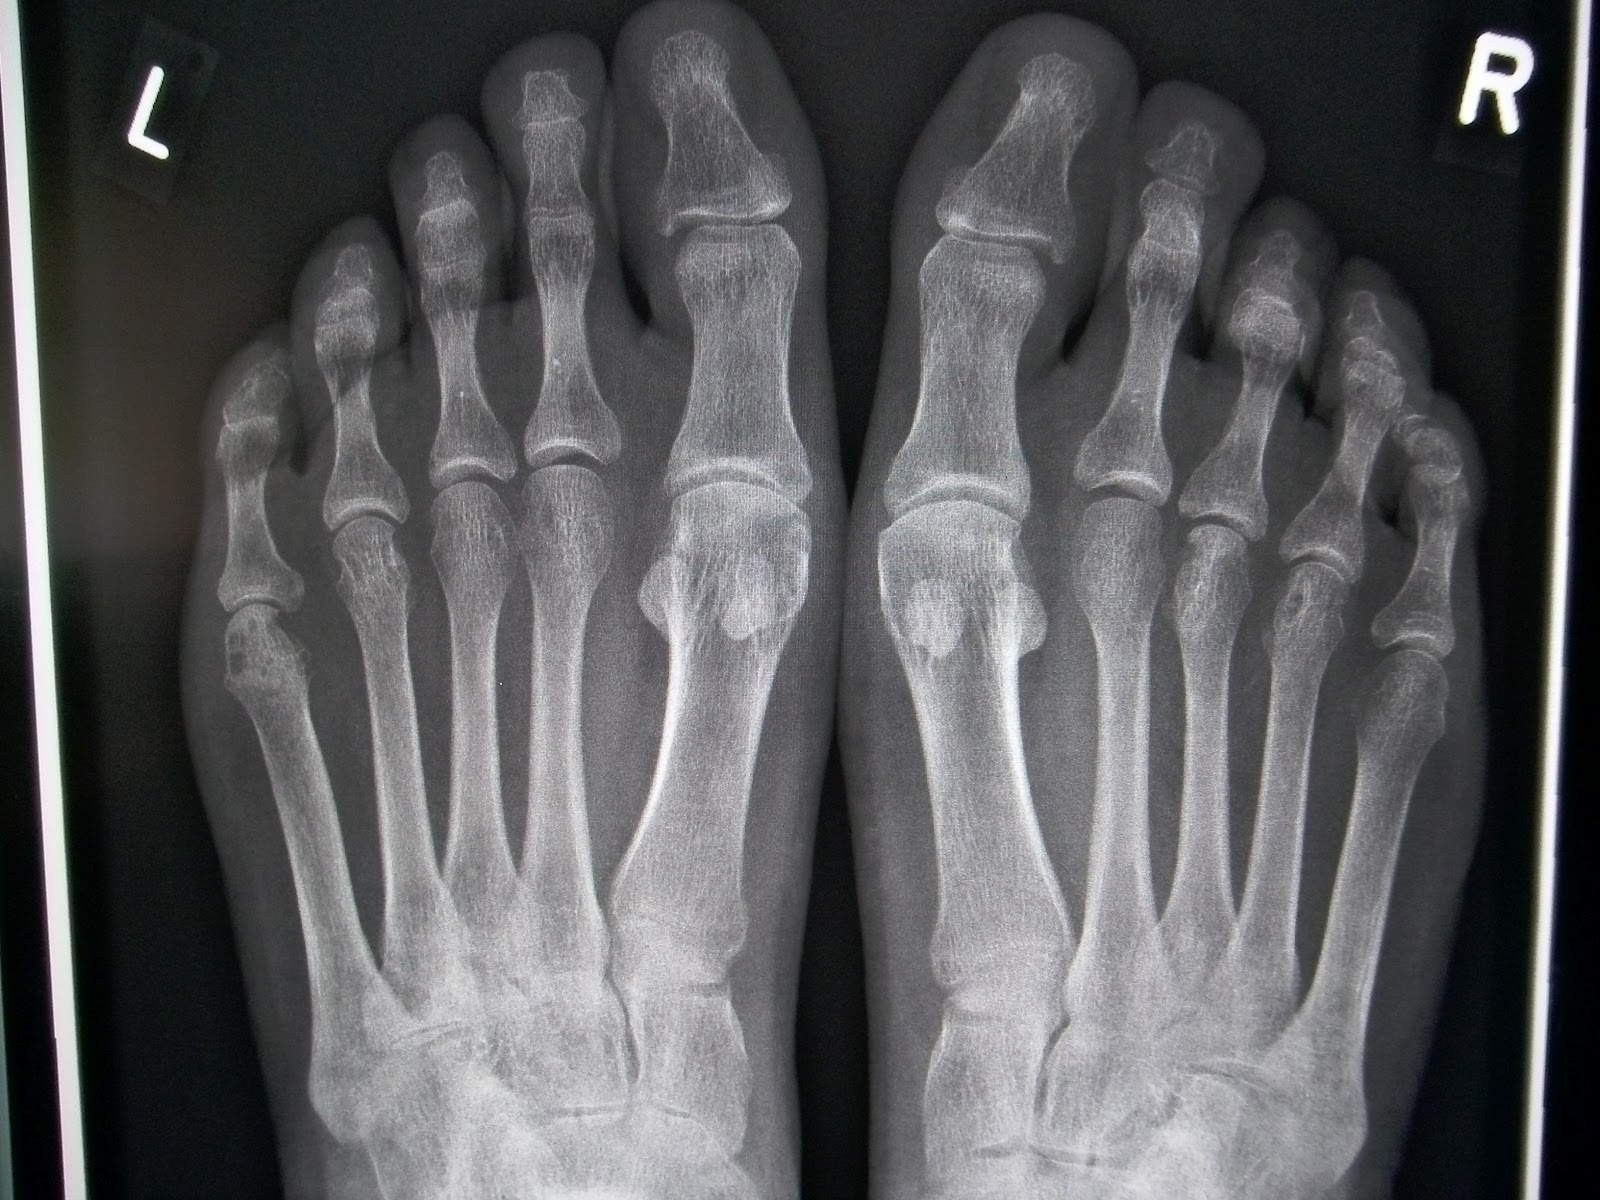

Артрит стопы: визуализация симптомов и лечения